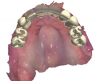

Fig 4. Intraoral surface scans with the patient’s removable partial denture in place; frontal view (Fig 4), and occlusal view (Fig 5).

Fig 5. Intraoral surface scans with the patient’s removable partial denture in place; frontal view (Fig 4), and occlusal view (Fig 5).

She used a removable partial denture, which was stable and fit well, to replace her missing maxillary posterior teeth. A CBCT scan (Fig- ure 3) and intraoral surface scans, including maxillary, mandibular, and centric record scans, were taken (Figure 4 and Figure 5). The prognosis of her remaining maxillary teeth was poor with a very low probability of any reasonable long-term success for a maxillary full-arch fixed restoration utilizing her maxillary teeth.

To begin the treatment, the following data were sent to the dental laboratory: the initial intraoral surface scans, which included a scan of the maxilla with the patient's removable partial denture in place (Figure 4 and Figure 5); a second intraoral surface scan of the maxilla without the maxillary removable partial denture; an intraoral surface scan of the mandible and a virtual centric record; and the treatment plan, which identified the teeth that would be kept to serve as provisional abutment teeth and the ideal implant positions. In this case, the teeth selected to serve as provisional abutment teeth were Nos. 6, 10, and 11. The laboratory made virtual crown preparations for these teeth and manufactured PMMA shell provisional crowns with a CAD/CAM process.